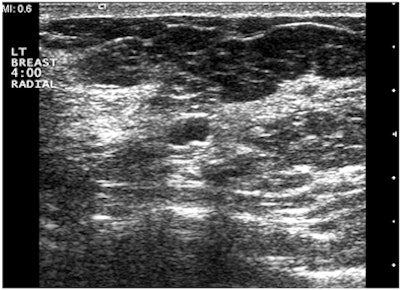

"A simple, yet powerful application of PDUS is differentiating between a rounded, markedly hypoechoic tumor and a [thickened] cyst with low-level internal echoes," he said. "The detection of the smallest vessel within the lesion automatically excludes a cyst -- or any other fluid collection -- and confirms a neoplasm. This very simple yet very useful application of PDUS is still underused."

| Images are of a circumscribed round pseudocystic mass. Above, grayscale US shows a cystic appearing mass with some low-level internal echoes. Below, PDUS performed with only minimal pressure applied through the probe shows internal vascularity, thereby excluding a fluid-filled lesion and confirming a tissular mass. Fine-needle aspiration readily confirmed a metastasis from a uterine leiomyosarcoma treated six years previously. All images courtesy of Dr. Bruno Fornage. |